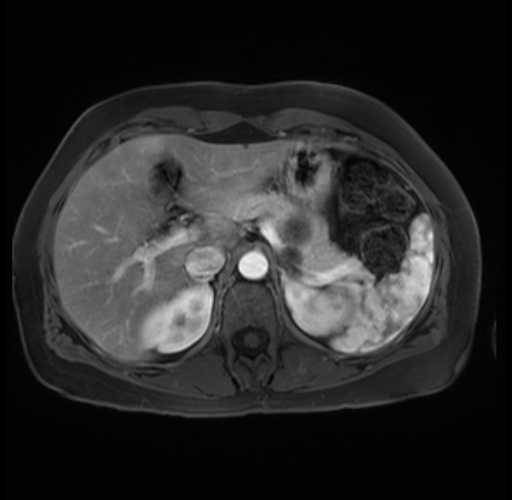

Imaging Analysis

Look through the patient's CT scan to identify any areas of concern for the necessary procedure.

Based on your CT findings, which issue(s) are present and would give reason for "planned slowing down moment(s)" in this case?

Considering a standard distal pancreatectomy procedure, what step(s) of the operation would you do differently in this case?